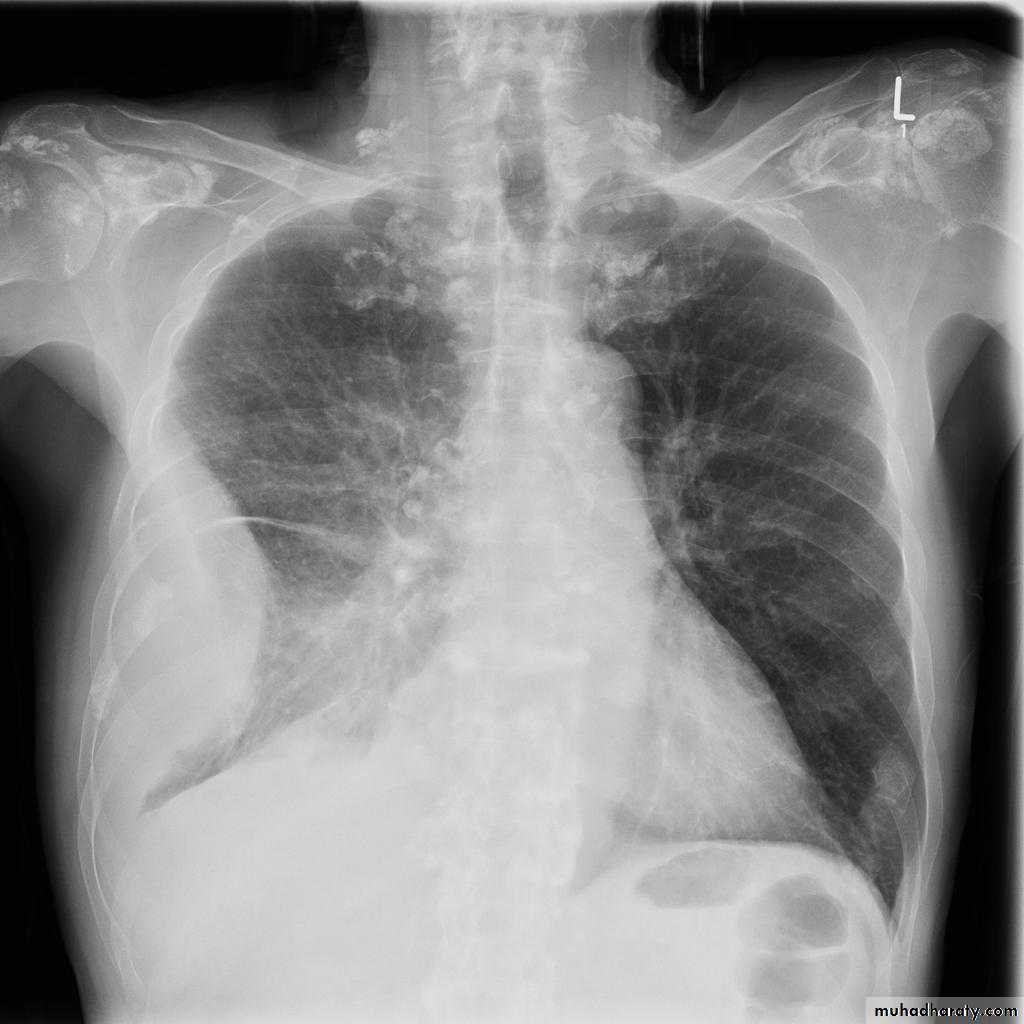

Miliary TB

65.Miliary TB

66. miliary TB